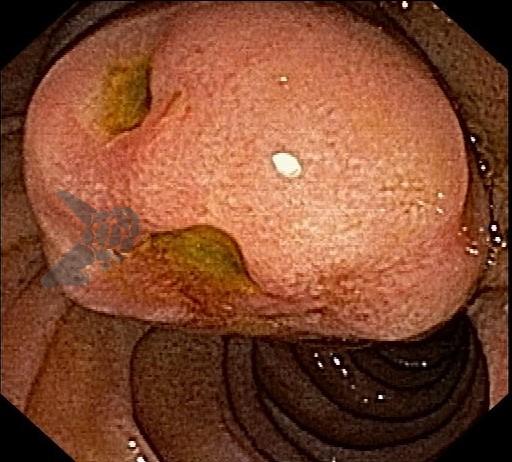

Figuras 1 e 2. Imagem endoscópica em visão direta de lesão protrusa entre pequena curvatura e parede posterior de corpo gástrico proximal, revestida por mucosa com superfície regular, normocorada e íntegra. A imagem ecoendoscópica demonstra lesão com ecogenicidade hipoecoica, ecotextura homogênea, formato ovalado, sem características internas, sem vascularização ao doppler, limites precisos, contornos regulares, medindo aproximadamente 20 x 6 mm e inserida em camada muscular própria. Punções ecoguiadas foram realizadas com agulha FNB, sendo o anatomopatológico e imuno-histoquímica compatíveis com GIST gástrico. Fonte: arquivos do Instituto do Câncer do Estado de São Paulo (ICESP/HCFMUSP)Figuras 1 e 2. Imagem endoscópica em visão direta de lesão protrusa entre pequena curvatura e parede posterior de corpo gástrico proximal, revestida por mucosa com superfície regular, normocorada e íntegra. A imagem ecoendoscópica demonstra lesão com ecogenicidade hipoecoica, ecotextura homogênea, formato ovalado, sem características internas, sem vascularização ao doppler, limites precisos, contornos regulares, medindo aproximadamente 20 x 6 mm e inserida em camada muscular própria. Punções ecoguiadas foram realizadas com agulha FNB, sendo o anatomopatológico e imuno-histoquímica compatíveis com GIST gástrico. Fonte: arquivos do Instituto do Câncer do Estado de São Paulo (ICESP/HCFMUSP)Figuras 3 e 4. Imagem endoscópica em visão direta de abaulamento de parede em segunda porção duodenal distalmente à papila duodenal maior, revestida por mucosa com íntegra, de coloração amarelada e superfície regular. A ecoendoscopia demonstra lesão com ecogenicidade hiperecoica, ecotextura homogênea, formato arredondado, medindo cerca de 10 mm no maior eixo, com limites precisos, contornos regulares, medindo cerca de 10 mm no maior diâmetro e inserida em camada submucosa, sendo os achados endoscópicos e ecoendoscópicos compatíveis com lipoma.Figuras 3 e 4. Imagem endoscópica em visão direta de abaulamento de parede em segunda porção duodenal distalmente à papila duodenal maior, revestida por mucosa com íntegra, de coloração amarelada e superfície regular. A ecoendoscopia demonstra lesão com ecogenicidade hiperecoica, ecotextura homogênea, formato arredondado, medindo cerca de 10 mm no maior eixo, com limites precisos, contornos regulares, medindo cerca de 10 mm no maior diâmetro e inserida em camada submucosa, sendo os achados endoscópicos e ecoendoscópicos compatíveis com lipoma.Fig. 5. Imagem endoscópica em visão direta de lesão protrusa em parede anterior de antro gástrico proximal, revestida por mucosa normocorada, com superfície regular, sendo sugestiva de lesão subepitelial.Fig. 6. A ecoendoscopia evidencia lesão com ecogenicidade hipoecoica, ecotextura predominantemente homogênea, formato arredondado, limites precisos, bordos regulares, medindo aproximadamente 13,4 x 12 mm, sem focos hiperecoicos ou calcificações no interior e inserida na camada muscular própria. Punções ecoguiadas foram realizadas com agulha FNB, sendo anatomopatológico e imuno-histoquímica confirmando schwanomma gástrico.Fig. 7 e 8. Imagem de esofagogastroduodenoscopia demonstra lesão protrusa em papila duodenal maior revestida por mucosa enantemática e com superfície com três erosões recobertas por fibrina.Fig. 7 e 8. Imagem de esofagogastroduodenoscopia demonstra lesão protrusa em papila duodenal maior revestida por mucosa enantemática e com superfície com três erosões recobertas por fibrina.Fig. 9 e 10. Imagem à ecoendoscopia demonstra lesão com formato ovalado, ecogenicidade hipoecoica, ecotextura heterogênea, com contornos regulares, sem adenopatia adjacente, sem vascularização ao doppler, sem características internas, medindo cerca de 20 x 11 x 24 mm, inserida na camada submucosa, não havendo acometimento da muscular própria. Foram realizadas punções ecoguiadas com agulha FNA 22 gauge, sendo o anatomopatológico e imunohistoquímica compatíveis com tumor neuroendócrino de papila duodenal bem diferenciado grau 1.Fig. 9 e 10. Imagem à ecoendoscopia demonstra lesão com formato ovalado, ecogenicidade hipoecoica, ecotextura heterogênea, com contornos regulares, sem adenopatia adjacente, sem vascularização ao doppler, sem características internas, medindo cerca de 20 x 11 x 24 mm, inserida na camada submucosa, não havendo acometimento da muscular própria. Foram realizadas punções ecoguiadas com agulha FNA 22 gauge, sendo o anatomopatológico e imunohistoquímica compatíveis com tumor neuroendócrino de papila duodenal bem diferenciado grau 1.Fig. 11 e 12. Esofagogastroduodenoscopia demonstra abaulamento de parede anterior de corpo gástrico proximal, com mucosa normocorada, superfície regular com depressão central, sendo compatível com lesão subepitelialFig. 11 e 12. Esofagogastroduodenoscopia demonstra abaulamento de parede anterior de corpo gástrico proximal, com mucosa normocorada, superfície regular com depressão central, sendo compatível com lesão subepitelialFig. 13 e 14. Ecoendoscopia demonstrou formação com ecogenicidade hipoecoica, ecotextura homogênea, formato ovalado, limites bem definidos, contornos regulares, medindo aproximadamente 13 mm e inserida na camada submucosa. Lesão foi submetida a ressecção endoscópica transmural com dispositivo FTRD. A histopatologia e imunohistoquímica confirmaram TNE gástrico bem diferenciado grau 2.Fig. 13 e 14. Ecoendoscopia demonstrou formação com ecogenicidade hipoecoica, ecotextura homogênea, formato ovalado, limites bem definidos, contornos regulares, medindo aproximadamente 13 mm e inserida na camada submucosa. Lesão foi submetida a ressecção endoscópica transmural com dispositivo FTRD. A histopatologia e imunohistoquímica confirmaram TNE gástrico bem diferenciado grau 2.